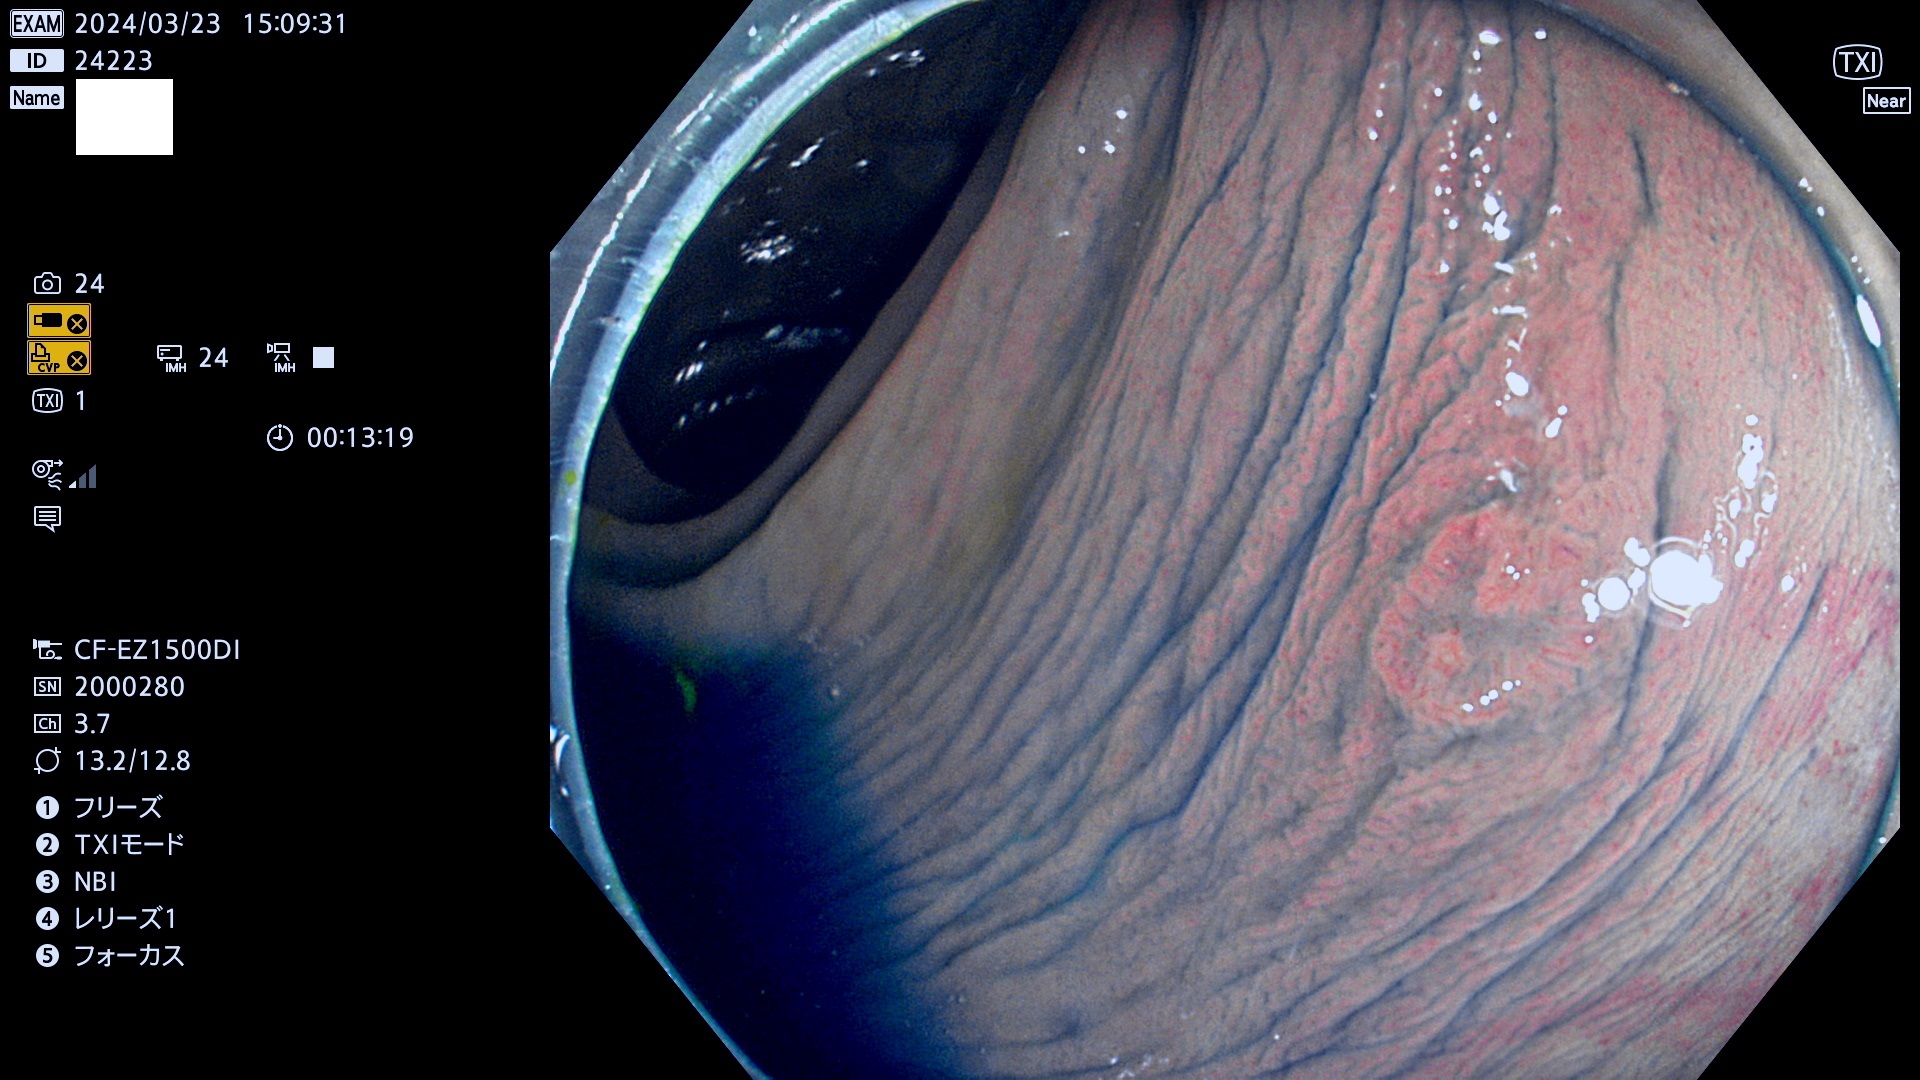

表面型腺腫(Flat Adenoma)の中で、完全に平坦な物をUb、陥凹している物をUcと呼びます。平坦隆起型(Ua)よりも、発見が難しく危険な病変です。

毎週の検査(木・金・土・日)に発見されたUb、Uc型・腺腫を、その週の日曜の夜にUPし1週間、提示します。

抽出の対象期間 2024年3月21日(木)〜3月24(日)の4日間(44件の検査)7件 (8/44=18%)

ビランと鑑別の困難な腺腫